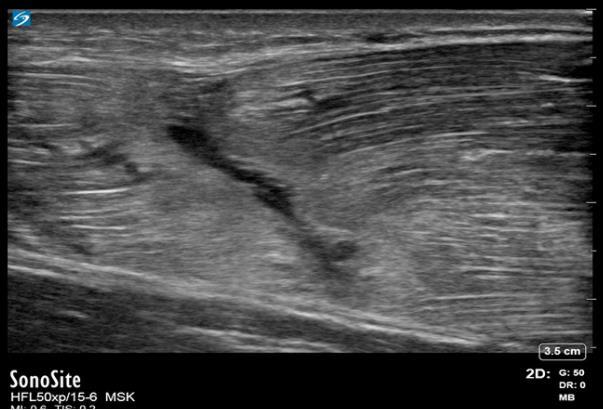

Image - Épaule : Déchirure du triceps